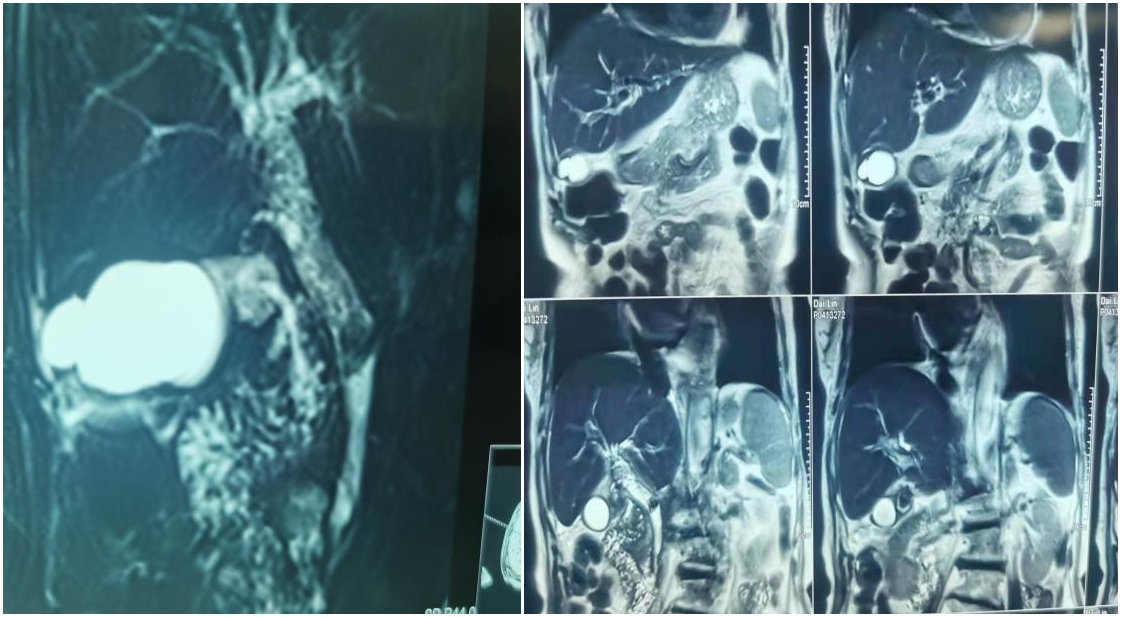

剛入院時,代奶奶體溫高達39.5℃,并且腹痛進行性加重,皮膚及鞏膜變黃,尿液濃茶水樣。代奶奶病情惡化非常迅速,主治醫生遂即給予胸部CT:雙肺間質性改變,肺氣腫伴右肺中下野感染;MRCP檢查回報:急性膽囊炎、膽囊結石頸部嵌頓、膽總管多發結石、急性膽管炎、腹水等。

危急關頭,必須立刻減除代奶奶的頸部結石嵌頓及膽管結石梗阻!考慮到患者高齡、合并癥較多,開刀取石風險很高。在科主任馬煜帶領下,邀請麻醉手術科、呼吸科、心內科會診,最終決定為代奶奶實施“腹腔鏡膽囊切除術+ERCP取石術”。

術中,可見膽囊張力大,滲出較多;膽囊與周圍粘連明顯,在主治醫生的仔細操作下,順利切除膽囊。膽囊切除手術后,在麻醉手術室醫護人員的協助下,為代奶奶實施了ERCP手術。